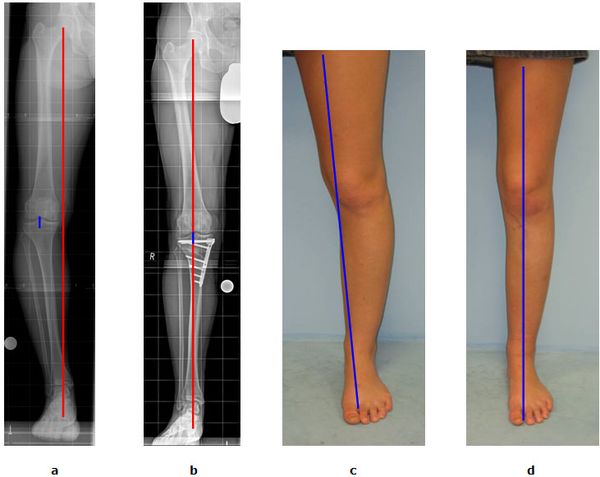

Abb.1: a Die mechanische Beinachse (rote Linie) verläuft nicht mehr durch die Kniegelenksmitte (blaue Linie) sondern ist nach Innen verlagert. Es handelt sich um eine O-Bein Fehlstellung. Der Innere Gelenkspalt ist bereits hochgradig verschmälert (Varusgonarthrose).

b Durch eine Kniegelenksnahe Umstellung des Schienenbeins

(Tibiakopfosteotomie)verläuft die mechanische Beinachse wieder mittig. Die blaue und rote Linie decken sich. Der Innere Gelenkspalt ist entlastet.

c O-Bein Stellung vor der Operation.

d Die Begradigung durch den Eingriff ist offensichtlich.